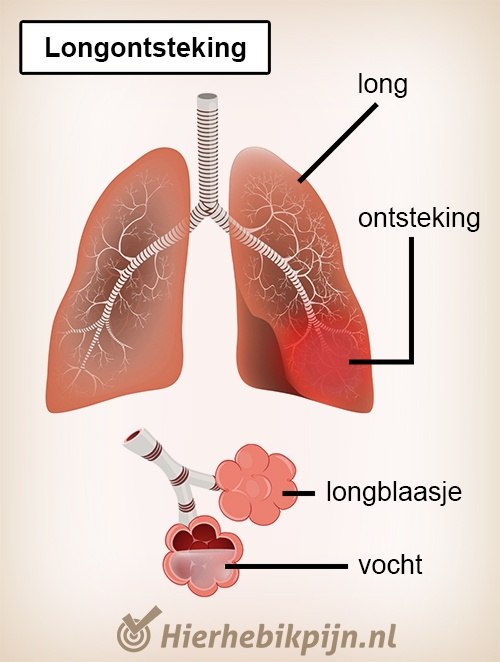

Longontsteking en bronchopneumonie. Infectie van het longweefsel vormt een longontsteking, maar als ook de kanalen (bronchi) die de lucht in de longen laten stromen aangetast zijn, spreekt men van bronchopneumonie. De oorzaken van deze infectie van de lagere luchtwegen zijn virussen, bacteriën en zelfs schimmels.

Longontsteking Klachten Hier Heb Ik Pijn

Longontsteking symptomen en remedies YouTube